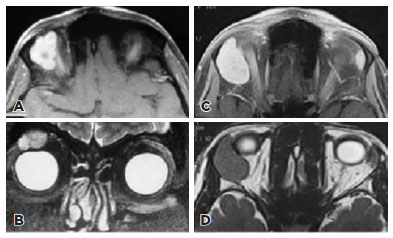

The clinical and radiologic findings of the11 PAs and 16 ACCs were evaluated (Tables 1-2). There were no significant differences between groups in terms of age or sex. Although there was no significant difference in terms of proptosis, palpable mass, diplopia, sensory loss, or persistent pain between PAs and ACCs, these clinical symptoms were observed relatively more often in ACCs in our study. The mean duration of symptoms was significantly longer in the PA group (p=0.001);notably, duration was longer than 120 months in 5 patients with PA. Proptosis was the most common presenting symptom in both groups (90% in PA vs. 87.5% in ACC).All lacrimal gland lesions were isointense relative to extraocular muscle on CT. There were no statistically significant differences in terms of homogeneity and globe indentation between lacrimal gland PAs and ACCs on CT (p>0.05). Bone invasion, wedge sign, and calcification were observed significantly more often in ACCs, while bone remodeling was significantly more common in PAs on CT (all p<0.05). PAs were significantly more likely to show well-defined margins, lobulated contour, heterogeneous contrast enhancement, and hyperintensity on T2-weighted MRI (all p<0.05; Figures 1-2).

11-fig02.jpg)

On MRI, PAs may appear as lobulated masses. In the presente study, lobulation of the contour was observed in 10 of 11 of PA patients; in contrast, none of the ACC patients showed lobulation of the contour in our series. Lobulated contours may thus be a specific feature for distinguishing PAs from malignant epithelial lacrimal gland tumors. Mărgăritescuet al.(29) reported that PAs (prominently myxoid areas) often had incomplete capsules and tumors with characteristics that might be expected to have lobulated contours on MRI. Although there was no significant difference in T1-weighted MRI between PAs and ACCs in our study, the isointense signal density was relatively higher in ACCs. In the literature, isointensity on T1-weighted images has been observed in both epithelial and non-epithelial tumors at a similar rate(8,25), and is thus not a differentiating feature for lacrimal gland tumors. In our study, PAs were more likely to present with a bright signal on T2-weighted MRI and heterogeneous nodular enhancement than ACCs. Similarly, Watanabe et al.(6) and Gündüz et al.(30) both reported high intensity in PA cases and a greater likelihood of contrast heterogeneous enhancement. Tsushima et al.(31) reported the histologically myxoid areas of pleomorphic adenoma to be the cause of bright intensity signals on T2-weighted MRI. Young et al.(7) reported that PAs showed high intensity on T2-weighted MRI and heterogeneous contrast enhancement in their series, but stated that lacrimal gland malignant epithelial tumors were more likely to have heterogeneous contrast enhancement compared with PA. However, the MRI findings of ACC, which is a subgroup of malignant epithelial tumors of the lacrimal gland, were not evaluated in that study as a separate group(7). Thus,T2-weighted images may be more valuable than T1-weighted images for differential diagnosis of such patients.